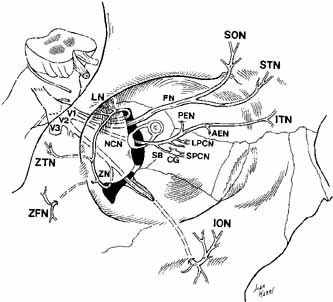

third meets the anterior two-thirds. Trigeminal Nerve (V) The ophthalmic and maxillary divisions of the sensory trigeminal nerve

enter the orbit and pass through to supply the superior two-thirds

of the face (Figs. 19 and 20) . The ophthalmic division enters the orbit through the superior

orbital fissure as three branches: the lacrimal, frontal, and nasociliary. The

lacrimal nerve is the smallest branch, and it passes into the

orbit through the lateral end of the extraconal superior orbital fissure (see Figs. 6 and 19). It joins the lacrimal artery to reach the posterior aspect of the

lacrimal gland. Here, it forms superior and inferior branches; the

former supplies the gland, conjunctiva, and the lateral upper eyelid. The

inferior branch anastomoses with the zygomaticotemporal branch of

the maxillary trigeminal nerve, where it picks up parasympathetic secretory

fibers to the gland. The frontal branch passes just beneath the

periorbita, where it divides anteriorly in the orbit to form the supratrochlear

and larger supraorbital branch, which supply sensation to the

medial canthus, upper lid, and brow areas (see Fig. 19). The supraorbital nerve should be identified and spared during dissection

of the supraorbital rim, transcoronal forehead orbital approaches, or

during forehead lifts. The nasociliary branch of the ophthalmic

division is the only one to pass through Zinn's annulus. It passes

over the optic nerve with the ophthalmic artery to lie between the

superior oblique and medial rectus muscles. The nasociliary nerve gives

off a sensory route to the ciliary ganglion, two or three long ciliary

nerves to the globe, the anterior and posterior ethmoidal nerves

to supply the nasal mucosa, and the terminal infratrochlear branch to

supply the tip of the nose (Fig. 21). Involvement of this terminal infratrochlear branch of the nasociliary

nerve in herpes zoster ophthalmicus is termed Hutchinson's sign.  Fig. 19 Schematic drawing of the trigeminal nerve course in the orbit. (V1, Vl nerve; V2, V2 nerve; V3, V3 nerve; FN, frontal nerve; SON, supraorbital nerve; STN, supratrochlear nerve; LN, lacrimal nerve; ZTN, zygomaticotemporal nerve; ZFN, zygomaticofacial nerve; ZN, zygomatic nerve; NCN, nasociliary nerve; SB, sensory branch to the ciliary ganglion; CG, ciliary ganglion; SPCN, short posterior ciliary nerves; LPCN, long posterior ciliary nerves; PEN, posterior ethmoidal nerve; AEN, anterior ethmoidal nerve; ITN, infratrochlear nerve; ION, infraorbital nerve) Fig. 19 Schematic drawing of the trigeminal nerve course in the orbit. (V1, Vl nerve; V2, V2 nerve; V3, V3 nerve; FN, frontal nerve; SON, supraorbital nerve; STN, supratrochlear nerve; LN, lacrimal nerve; ZTN, zygomaticotemporal nerve; ZFN, zygomaticofacial nerve; ZN, zygomatic nerve; NCN, nasociliary nerve; SB, sensory branch to the ciliary ganglion; CG, ciliary ganglion; SPCN, short posterior ciliary nerves; LPCN, long posterior ciliary nerves; PEN, posterior ethmoidal nerve; AEN, anterior ethmoidal nerve; ITN, infratrochlear nerve; ION, infraorbital nerve)

The maxillary division of the trigeminal nerve exits the foramen rotundum

and crosses the pterygopalatine fossa before entering the orbit through

the inferior orbital fissure. The main component of the second division

of the trigeminal nerve is the infraorbital nerve that courses

anteriorly to enter the infraorbital groove 2.5 to 3 cm posterior to the

orbital rim, traverses the infraorbital canal, and then emerges from

the infraorbital foramen to provide sensation to the lower eyelid, cheek, and

upper lip (see Figs. 19 and 20). Sphenopalatine and posterior superior alveolar branches are formed

in the sphenomaxillary fossa to provide sensation to the nasal mucosa, gingiva, teeth, and

upper lip; middle and anterior superior alveolar

branches arise in the infraorbital canal. The zygomatic branch of

the maxillary nerve enters the inferior orbital fissure and divides into

the zygomaticotemporal and zygomaticofacial nerves, with the former

carrying parasympathetic secretory fibers from the sphenopalatine ganglion